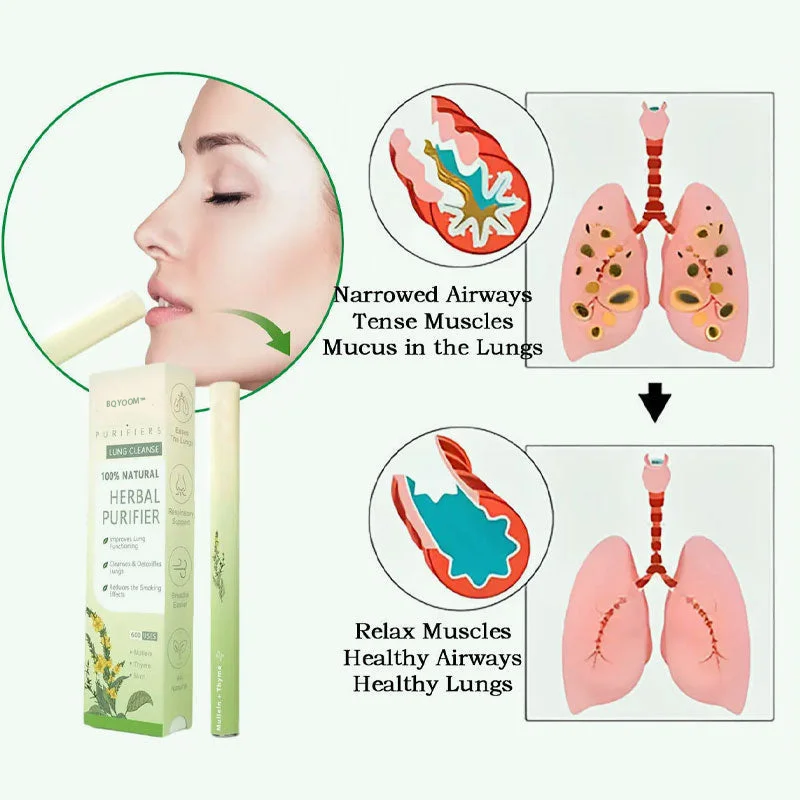

🌿 How It Works

BQYOOM™ Mullein Diffuser: Combining nature and science to help you breathe better.

🌸 Mullein (Breathe Essence B3): Helps clear airways, promotes smoother breathing, and reduces respiratory discomfort.

🍃 Thyme: Purifies the air, supports healthy breathing, and creates a more comfortable environment.

🌿 Mint: Eases breathing discomfort, Mitigates the throat, and provides long-lasting freshness.

Achieve Smoother Breathing and a Healthier Lifestyle with 6 Key Benefits.

BQYOOM™ Mullein Diffuser: Combines natural ingredients to support better breathing and healthier living.

Soothing and Calming: Helps reduce respiratory discomfort and relax the body.

Respiratory Relief: Clears the airways, improving overall breathing.

Antioxidant Properties: Supports healthy airflow and helps neutralize pollutants in the air.

Anti-inflammatory Effects: Eases discomfort and promotes smoother breathing.

Purifying Aroma: Clears nasal passages and improves air quality.

Naturally Safe: Free from harmful chemicals, offering a safe and effective solution for daily use.

The BQYOOM™ Mullein Diffuser strikes the perfect balance of nature and science to make every breath feel easier and fresher.